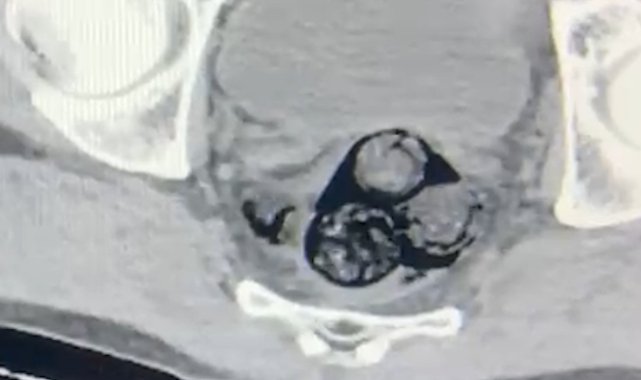

Iğdır'da, narkotik suçlarla mücadele kapsamında gerçekleştirilen bir operasyon sonucunda, vücut boşluklarında uyuşturucu taşıyan yabancı uyruklu bir şahıs tutuklandı.Iğdır İl Emniyet Müdürlüğü Narkotik Suçlarla Mücadele Şube Müdürlüğü ekipleri, yurt dışından Türkiye'ye giriş yapan ve şüpheli hareketler sergileyen A.İ. isimli kişiyi takibe aldı. Yapılan detaylı aramalar neticesinde, şahsın vücut boşluklarında uyuşturucu madde taşıdığı belirlendi. Radyolojik görüntüleme sonucu, şüphelinin makat bölgesinde dört farklı yabancı cisim olduğu ortaya çıktı. Sağlık kontrolünden geçirilerek, çıkarılan cisimlerin içinde toplamda 140 gram metamfetamin olduğu tespit edildi. Uyuşturucu madde taşımak ve ticaretini yapmak suçundan hakkında işlem başlatılan A.İ., Iğdır Adliyesi'ne sevk edildi. Mahkemeye çıkarılan şahıs, tutuklanarak cezaevine gönderildi.